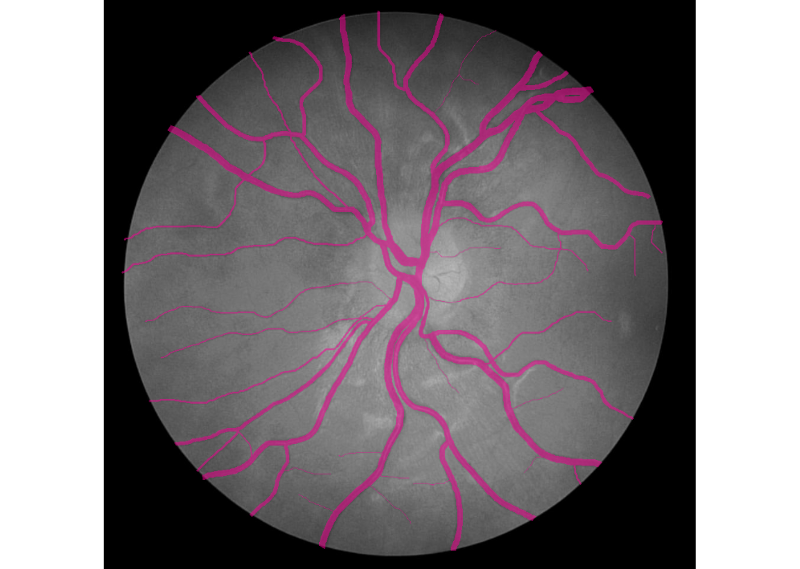

Hello world! In December of 1895, Wilhelm Röntgen the bones of his wife’s hand in the first X-ray photograph. “I have seen my death,” she said. This breakthrough had an incredible influence on 20th-century medical treatment. And latest Deep Learning advances open up new possibilities in this field. revealed Deep Learning has found great success in computer vision and other areas. And now it is actively transforming the world of medicine. AI helps doctors make more accurate diagnoses faster. Today we would like to share our thoughts and investigations into very promising direction: Human in the loop AI for medical image analysis within a single environment — . Supervisely Our platform allows to manage and annotate data, train NNs, apply them for automatic pre-annotation and then deploy them as API. Challenges with medical images IBM researchers that medical images, as the largest and fastest-growing data source in the healthcare industry, account for at least 90 percent of all medical data. estimate Challenge 1: data privacy Medical data is still personal and not easy to access. And due to data privacy concerns most of the public health centers are reluctant to share the data. Challenge 2: size of annotated data Annotation process is hard to outsource and only expert physicians can analyze medical images. This limitation leads to high costs and to the lack of annotated data. Challenge 3: quality of annotation tools Annotation tools, that can be used to extract insights from medical images, are still limited, in most cases publicly unavailable and requiring most analysis to be done manually. Challenge 4 (consequence of 1 and 2): segmentation challenge Datasets for segmentation task are typically extremely small compared to large public datasets of common images (COCO, PascalVoc and so on). Due to the size of datasets it is difficult to train very deep neural network architectures. Objects of interest can vary in size, shape and position. In combination with the “soft” boundaries it produces additional problems. Our goals We are going to overcome Challenge 3 and Challenge 4: give the industry end-to-end solution that makes human experts more efficient and automates routine tasks with powerful AI technologies. Supervisely: user interfaces We realize, that there is still a lot of work ahead: increase the number of convenient annotation tools and add the support of DICOM format, three dimensional images, sequences of images and so on. But these are only technical issues, first steps are already done and promising results are obtained. We are passioned to accelerate medicine and happy to be a part of global research community that drives deep learning revolution to healthcare. There could be no more important application of this new capability [deep learning] than improving patient care — Jensen Huang, NVIDIA CEO and co-founder Case-study: blood vessel segmentation in retina images There are a lot of Deep Learning medical applications in imaging: tumor detection, tracking tumor development, blood flow quantification and visualization, dental radiology and much more. Because we are not doctors, we looked for data we understand more or less. That’s why we decided to make research on blood vessel segmentation. Let’s take a look to one of the most popular public datasets in this field: (STructured Analysis of the Retina). STARE Dataset contains 28 annotated images with resolution 999 × 960. We consider the case that we have only . Other images will be used for final evaluation of quality. All training images are below: 6 annotated images in training dataset Here is the whole training dataset we use. This scenario is pretty close to real world: medical doctor annotates few images, then neural network is trained on this data and applied to other images for pre-segmentation. Then doctor just corrects the NN predictions. Such approach is called Human in the loop AI. It is aimed to significantly accelerate efficiency of human expert. PS. Thanks to Supervisely entire research took 2 hours without haste ☕. Step1: training data augmentation We had only 6 annotated images. To train NN we have to automatically increase the size of dataset. Supervisely has special module to perform augmentations: DTL (Data Transformation Language). It allows to configure entire augmentation process in a simple json-based format and perform it in a few clicks. How DTL query interface looks like In this use case we did horizontal/vertical flips and relatively big random crops. We got 264 training examples from only 6 annotated images. Here is the visualization of computational graph that we applied to our data: Resulted crops after augmentation Step2: train neural network There are few state of the art Neural Networks for semantic segmentation in Supervisely. One of them — our custom UNet-like architecture. It was chosen because: we have small training dataset, it is accurate and fast to train. Also we use combination of Binary Cross Entropy and Dice losses because of class imbalance problem. Vessels pixels covers only few percents of image area in contrast to background pixels. We trained NN 50 epochs. It is interesting to visualize Neural Network predictions during training. We take unseen image and apply NN after each epoch. Here you can see how our NN becomes smarter over time. Supervisely supports multi GPU training. Each epoch takes around 20 seconds on four GPU. Total training time — around 17 minutes. Step3: automatic pre-segmentation We applied NN to new images. Let’s compare predictions with ground truth. : NN predictions, : ground truth Left Right As you can see from this comparison every relatively bold vessels are segmented. There is no noise. It means that the human only have to draw few hairlines with “polyline” tool. Also, as we understand real data has much bigger resolution that public data we use in this experiment. We think that this fact is crucial for the quality of hairlines segmentation. Resolution of publicly available images is not enough. Look at this example: do you see the vessels that are annotated by doctors? Left: meme, Middle: original image, Right: doctor’s annotation Step4: manual correction As you can see from images above the quality of automatic pre-annotation is pretty good. It is much more easier and faster to correct NN predictions than annotate from scratch manually. We were not lazy and made time measurements: how much time we need for manual annotation from scratch vs correction of NN predictions. Manual annotation from scratch: . Correction of NN predictions: . 36 minutes / image 4 minutes / image Conclusion is obvious. Final thoughts Deep Learning has a huge potential in medical image analysis. AI is changing the way doctors diagnose illnesses. Main important difference between doctor and deep learning algorithm is that doctor has to sleep. Neural Network can process millions of images and can be continuously improved. Human in the loop approach and automatic segmentation with Supervisely will let us create large datasets faster. All steps are done without coding. It means that user with no ML background have access to state of the art AI. So ML community will build more services to help doctors provide better and quicker treatment. Let’s make the future together. If you found this article interesting, then let’s help others too. More people will see it if you give it some 👏.